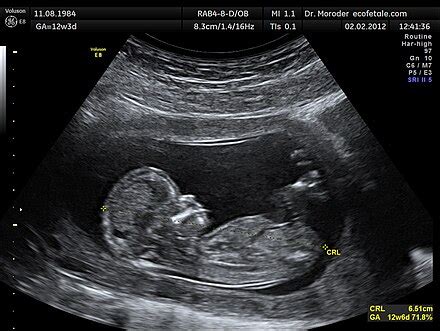

A normál lefolyású várandósságok körülbelül 3-4 százalékában a baba nem fejvégű fekvésben, hanem úgynevezett farfekvésben helyezkedik el a szülés idején. Ennek szakmai neve a medencevégű fekvés, a kismamák felé azonban gyakran „faros babaként” kommunikálják, mert ez közérthetőbb. A probléma ott kezdődik, hogy a leleteken általában csak a „farfekvés” kifejezés szerepel, miközben ennek több, egymástól lényegesen eltérő típusa van, és a pontos típus határozza meg, van-e lehetőség fordításra, szóba jöhet-e a hüvelyi szülés, és milyen kockázatokkal kell számolni.

A legtöbb nő nem tapasztalhat specifikus tüneteket, amelyek a farfekvéses babára utalnának, mivel a magzat helyzetét gyakran a rutinszerű prenatális ellenőrzések során fedezik fel. A legtöbb nő nem vesz észre konkrét jeleket, de a szokatlan magzati mozgások, a megnövekedett medencei nyomás és a hátfájás farfekvéses pozícióra utalhat.